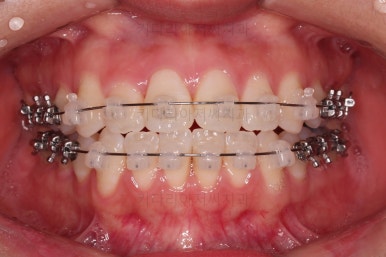

종료 시 사진입니다.

중앙선, 교합, 치아배열 모습 모두 양호해졌습니다.

부산교정잘하는치과 전후 비교해 보겠습니다.

치열도 당연히 좋아졌지만 웃을 때 보이는 치열도 매우 예뻐졌습니다.

입매도 본인이 원하는 수준으로 딱 멈춰드렸고, 적절하게 자연스럽게 약간 들어가고 마무리가 되었습니다.

전반적으로 매우 만족하신 치료가 되었습니다.